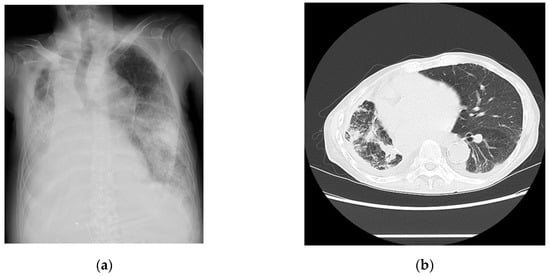

A 67-year-old man complaining of coughing and dyspnea was hospitalized with a diagnosis of COVID-19. He had a history of renal and lung cancers and pancreatic diabetes but no significant cardiovascular diseases. His vital signs upon admission are shown in Table 1. QT prolongation and ST-T changes are not shown (Table 1). The laboratory data are summarized in Table 2. An examination of the findings for this patient indicated that the levels of inflammatory markers were mildly elevated. The chest radiographs (Figure 3a) and computed tomography images (Figure 3b) revealed pneumonia. The echocardiographic findings are shown in Table 3. A 24 h Holter electrocardiography performed upon admission showed that all AECG-Ms were positive (Table 4). The patient was treated with heparin, remdesivir, and dexamethasone at a dose of 6.6 mg/day for 5 days. Oxygen saturation showed improvement on day 4 after admission, but the patient’s condition worsened from day 6, the BNP level increased from 162 pg/mL to 611 pg/mL, and carbon dioxide narcosis was induced. He was treated with methylprednisolone at a dose of 1000 mg/day for 3 days, remdesivir at a dose of 100 mg/day for 9 days, and heparin at a dose of 5000 U/day for 4 days, but he died from pneumonia with HFpEF on day 10 after admission.

Figure 3.

Imaging findings for Case 3 captured on day of admission. (a) Chest radiograph and (b) chest computed tomography image showing bilateral extensive findings of pneumonia with air bronchogram.